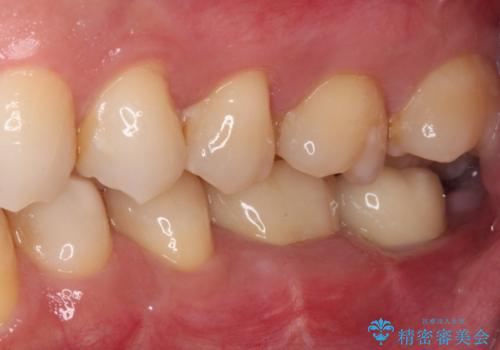

- 近医にて奥歯の抜歯が必要と言われたとのことで来院された患者様です。

診査の結果、歯が破折しており、抜歯が必要な状態でした。

最後方歯であるため、入れ歯かインプラントかどちらかの補綴治療を行うこととなりますが、ご希望によりインプラント補綴治療を行うこととしました。